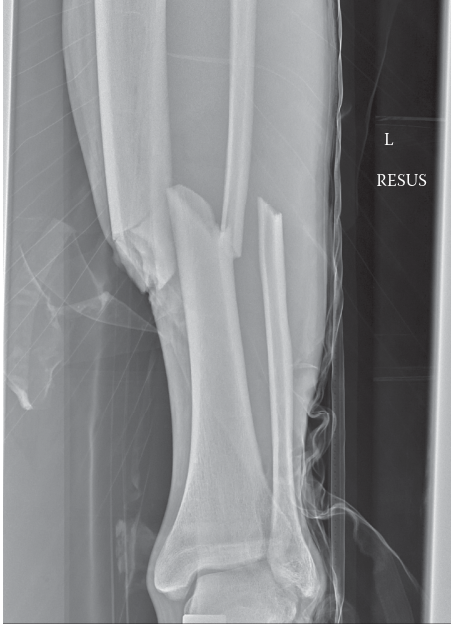

• Image demonstrating fracture reduction or entry point planning:

Image